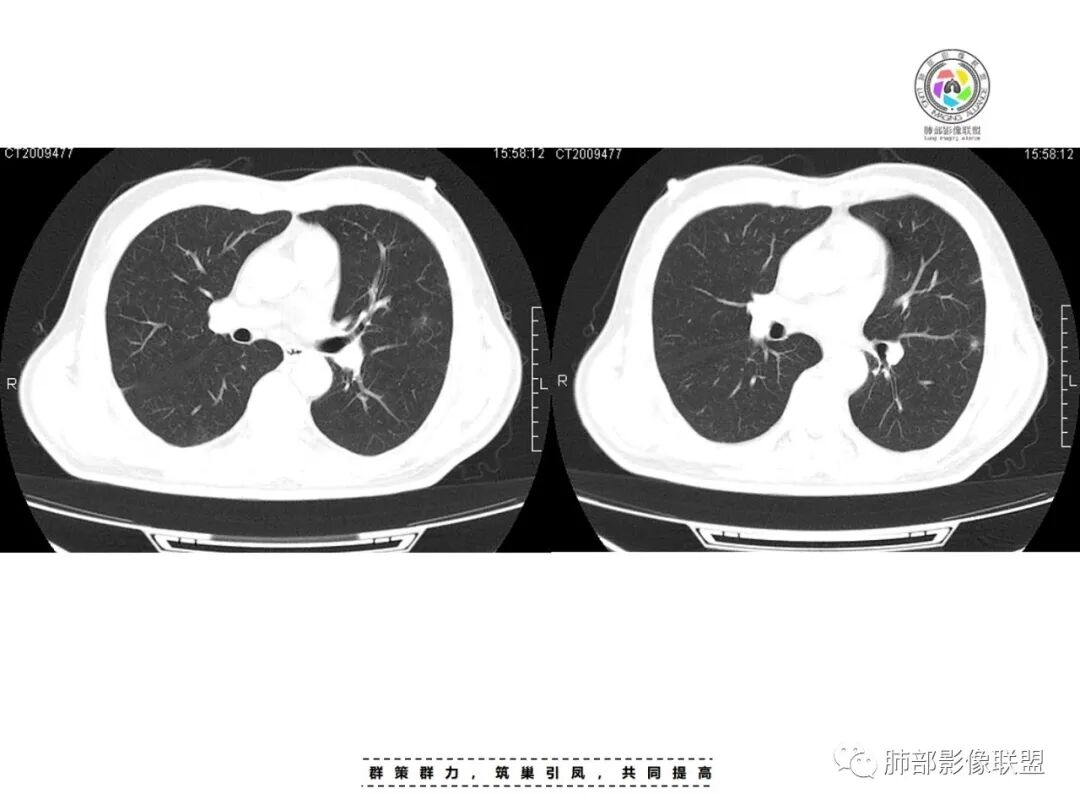

一、双肺多发结节或小片影,随机分布,而未见支气管壁增厚及支气管远端如树芽征等改变,提示病灶来源于血道;且肺内结节边缘模糊,常可排除转移(一般转移瘤边缘多较光整,患者常有恶性肿瘤病史,且呼吸道症状不明显或出现较迟);

首先看金葡菌,金葡菌多数要有皮肤受累感染才能入血,而该例没有相应病史,只是受凉。况且金葡感染患者易出现高热、病情进展更迅速,而该患者体温36.5摄氏度,不符合;影像上金葡更易短期内出现张力较高的薄壁气囊及脓胸等;所以金葡可能性较小。

其次看肺克雷伯杆菌,肺克易肠道入血,糖尿病病史始终是个危险因素,受凉可能暂时影响到糖尿病患者的免疫力,以此作为肺克发病的原因,似乎可以解释,但是患者体温不高,仍是一个存有疑惑的地方。

最后看临床资料,患者因受凉后咽干、咽痛,提示可能是条件致病菌,go and see老师提示很好,PCT升高不明显,基本就不考虑革兰氏阴性杆菌了,因为PCT的诱导过程中细菌内毒素(G-菌致病物质是内毒素)担任了至关重要的作用。因此该例细菌推断可能在非金葡菌的G+菌群中,如链球菌等。

影像表现:双侧结节,常伴空洞形成,最多见于肺外周和肺下野,结节的边界清晰或模糊;可伴有斑片状实变区;多表现为基底贴近胸膜的楔形实变影,其内密度均匀或不均匀,可形成空洞。